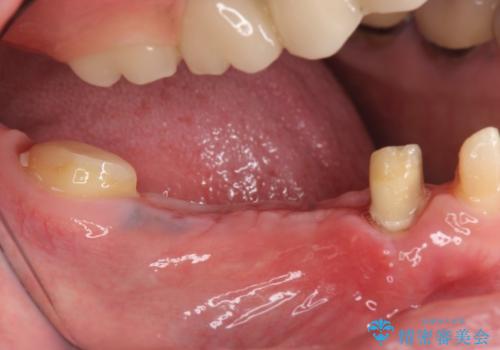

- 右下でものを咬むと痛むので診て欲しいといらっしゃった方の症例です。

右下6番目の歯を診査したところ歯根が破折していたため、保存不可能であることを説明し抜歯しました。

その後右下5、6番目にはインプラントを埋入し、右下3、4、5、6、7番の歯の補綴をオールセラミッククラウンによって行いました。